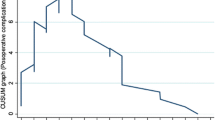

The receiver operating characteristic curve (ROC) was used to calculate a cut-off for CCS for both CT-PCI and S-PCI.

When the results were adjusted for CA-125 level, CPLNs, ascites, and days between the CT scan and surgery, the association was still significant (OR 1.069 (1.009–1.132), p < 0.023) (Table 3). The results were confirmed by ROC analyses, with an AUC of 0.715 (95% CI 0.609–0.822, p = 0.000) and generating a cut-off value of 21 for CT-PCI (Fig. 3). The sensitivity, specificity, positive predictive value and negative predictive value were 58.5% (CI 42.1–73.7%), 70.3% (CI 58.5–80.3%), 52.2% CI 41.3–62.7%) and 75.4% (CI 67.4–81.9%), respectively. The accuracy for CT-PCI ≥ 21 was 66.1% (56.67–74.65%).